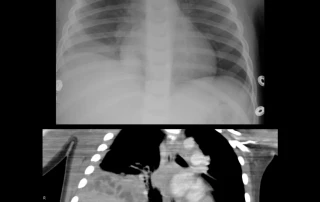

El empiema pediátrico representa una de las complicaciones más desafiantes de la neumonía bacteriana en la infancia.

Debemos sospechar esta entidad ante un paciente con neumonía que no presenta mejoría clínica tras 3 a 4 días de tratamiento antibiótico adecuado con amoxicilina, manifestando fiebre alta persistente y dificultad respiratoria progresiva. Al examen físico, la tríada clásica compuesta por matidez pétrea a la percusión, ausencia de ruidos […]